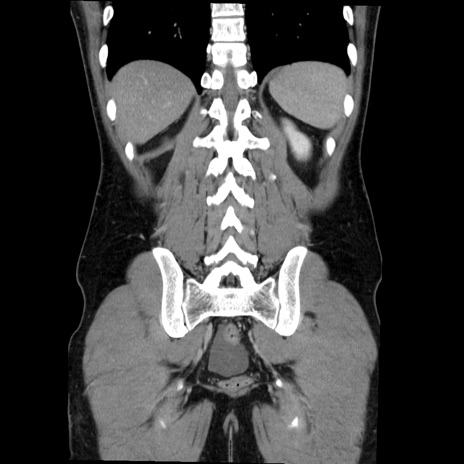

症例36(冠状断像)

【症例】20歳代 男性

【主訴】心窩部痛

【現病歴】今朝より上腹部痛あり。一旦軽快していたが再度出現したため救急要請。昨日夕に白身の魚を含む刺身を食べた。

【身体所見】BP 136/89mmHg、HR 74/min、BT 37.0℃、腹部:膨満、軟、心窩部に圧痛あり。反跳痛なし、筋性防御なし、腸雑音やや亢進あり。

【データ】WBC 17700、CRP 0.48